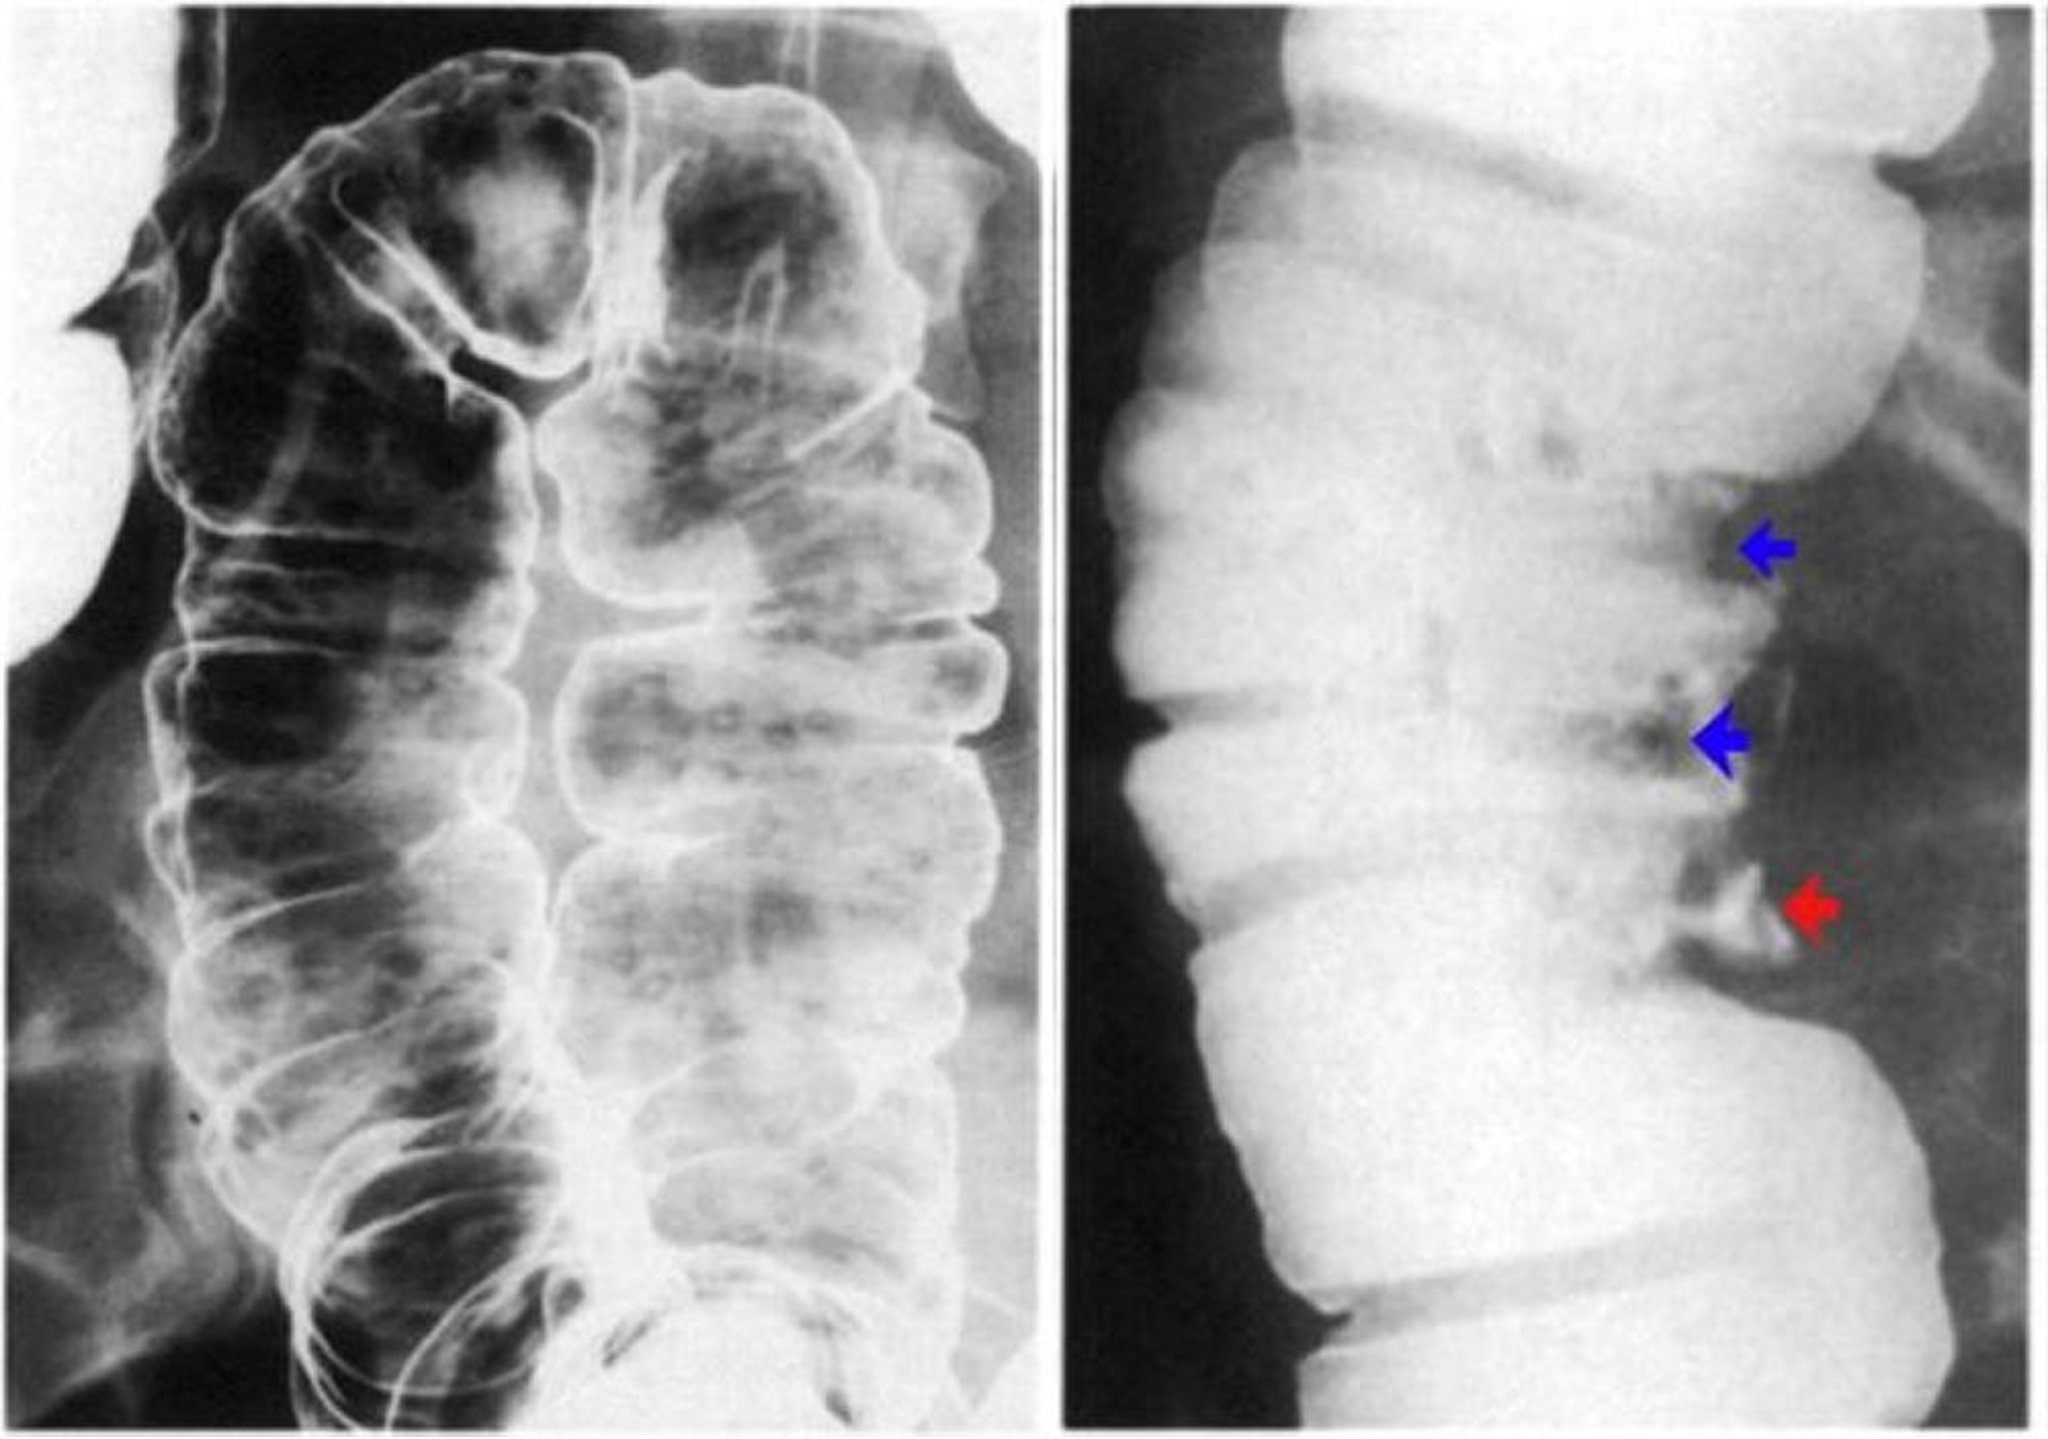

Enema baritado mostrando ulceração da parede do colo intestinal

A imagem à esquerda mostra úlceras aftosas. Há erosões discretas com um halo lucente sobre uma base de mucosa normal. Na imagem à direita, observam-se pseudopólipos demonstrados por defeitos de contraste (setas azuis) e também uma úlcera profunda (seta vermelha).